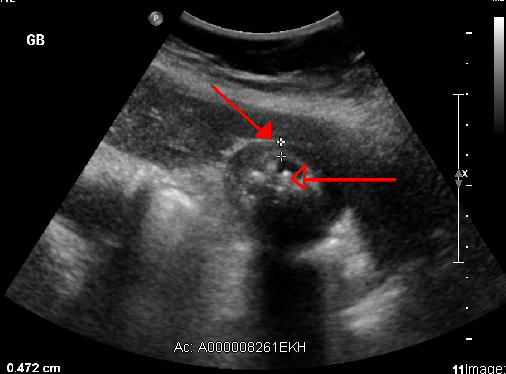

Gallstones

Gallstones are also called cholelithiasis.

The gallbladder contains solid, rounded stones because of precipitation of cholesterol (cholesterol stones) or bilirubin (bilirubin stones) in bile.

Cholesterol stones (yellow) are the most prevalent type (ninety percent), particularly in the West.

Gallstones are typically radiolucent (10 percent of gallstones are radiopaque because of associated calcium).

Bilirubin makes up the pigmented bilirubin stones.

Bilirubin stones are normally radiopaque.